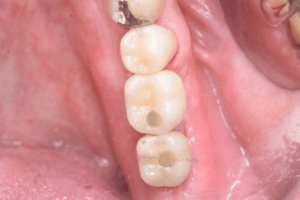

インプラント治療の症例6

レントゲン写真

- Before

- After

口腔内写真-1

- Befor

口腔内写真-2

口腔内写真-3

| 年齢 | 40代・女性 |

|---|---|

| 主訴 | 右下7番 |

| 治療内容 | インプラント埋入 |

| 治療費 | インプラント埋入料 440,000円 GBR(骨造成) 110,000円 サージカルガイド 55,000円 2次OPE 22,000円 静脈内鎮静麻酔 77,000円 合計 704,000円 (2023年4月現在) |

| 治療期間 | 1年 |

| リスク・副作用 | インプラント手術は外科処置のため、一過性、場合によっては持続的に唇・舌・頬・口蓋・歯肉・歯牙等の感覚麻痺、切開に起因する瘢痕組織による知覚異常が起こることがあります。 インプラント手術ではドリルのようなものを使用するため接近歯の損傷が起こる事があります。 インプラント体と骨との結合不全が起こる可能性があります。 痛みや腫れは個人差もありますが、約1〜2週間程度続きます。痛みは痛み止めを服用することでしのげる程度です。 |

| 治療方針 | 右下7番は一度根管治療済みでその後痛みが出て保存不可能と判断し、抜歯を行いインプラントになりました。 骨が元々少ないので、インプラント埋入と骨造成は同時に行わず、骨造成を先に行い骨が出来るのを待ってからインプラント埋入を行う2回法で行いました。 |

| 特記事項 | インプラントは人工物なので虫歯になることはありませんが、歯周病(インプラント周囲炎)にはなります。インプラントを長持ちさせるには、毎日の歯磨きと合わせて、3〜6ヶ月ごとの定期検診でのクリーニングが大切です。 |

| 担当者所見 | かみ合わせが強くマウスピースを進めましたが、本人はマウスピースが難しいため今後ボットクスで様子を見ていきます。 |